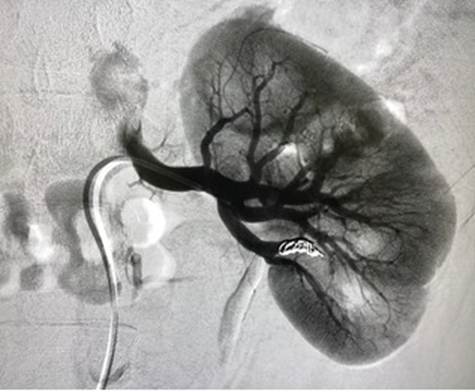

Arterial embolization

Arterial embolization is performed if kidney resection is not possible where the blood supply to the cancer is limited which stops the nutrient supply and allows the tumour shrink in size (Kidney Research UK, 2025)

Figure 11: The blood vessels of the kidneys (Creative commons, 2025)

Figure 12: Angiogram of the renal artery undergoing embolization (Shutterstock, 2025)